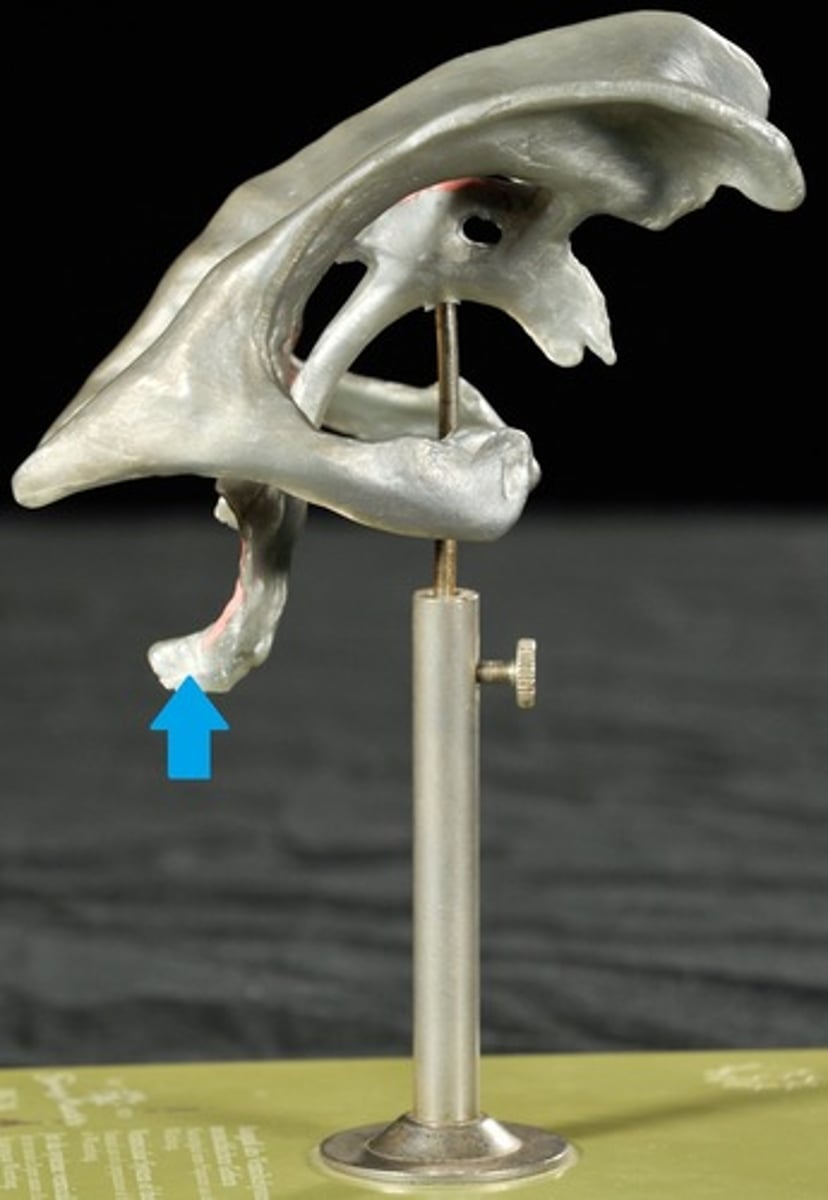

Traumatic brain injuries (head trauma)

1) a leading cause of accidental death in U.S.

2) Caused not only by localized injury at site of blow but also by ricocheting effect as brain hits opposite end of skull

Types of Head Trauma

Concussion,

Contusion,

Subdural Hematoma,

Cerebral Edema

Concussion

Alteration in brain function following blow to the head

Contusion

Bruising in the brain and can cause permanent Neurological Damage

Subdural Hematoma

Blood vessels are broken in the brain

Cerebral Edema

Swelling on the brain